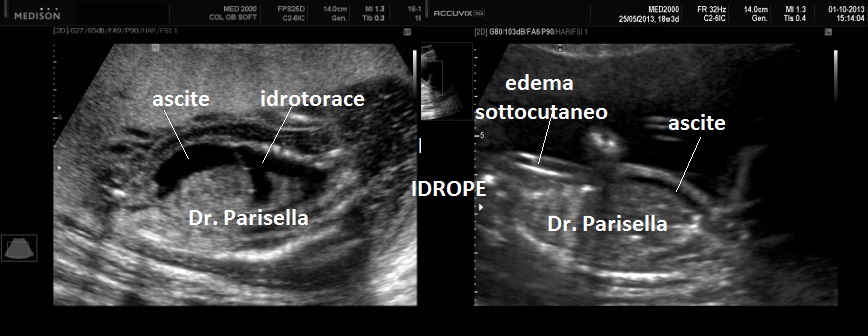

La forma grave (perinatale, infantile) è simile all'osteogenesi imperfetta tipo II con severo accorciamento degli arti (specie femore ed omero) la cui diafisi appare ricurva, ipoplasia toracica grave, ipomineralizzazione diffusa ad eccezione delle clavicole, idrope (nelle forme ad insorgenza precoce), polidramnios; incostantemente si hanno coste sottili e sedi di fratture.

MICROMELIA SEVERA, IPOPLASIA TORACICA SEVERA, IPOMINERALIZZAZIONE ESTREMA TRANNE LE CLAVICOLE, IDROPE (evidente principalmente nei casi a riscontro precoce), DEFORMAZIONE DELLA VOLTA CRANICA ALLA COMPRESSIONE IMPRESSA DALLA SONDA.